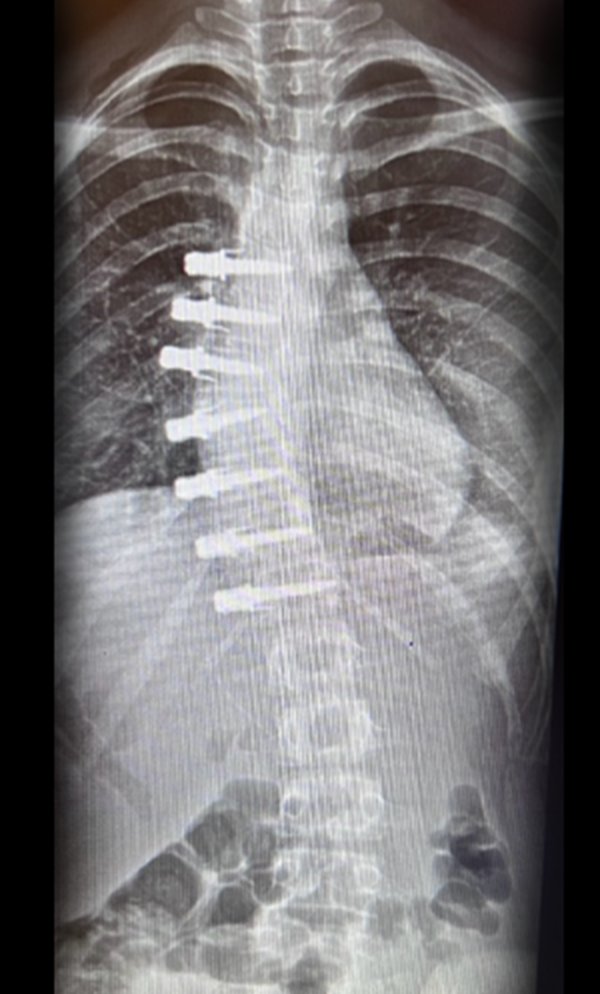

Gallery : Before - After

• Scoliosis surgery with small incisions using flexible correction technology (VBT) and growth-preserving techniques such as remotely controlled magnetic growing rods

• Scoliosis for children and adults

• Spinal fixation and fusion surgeries